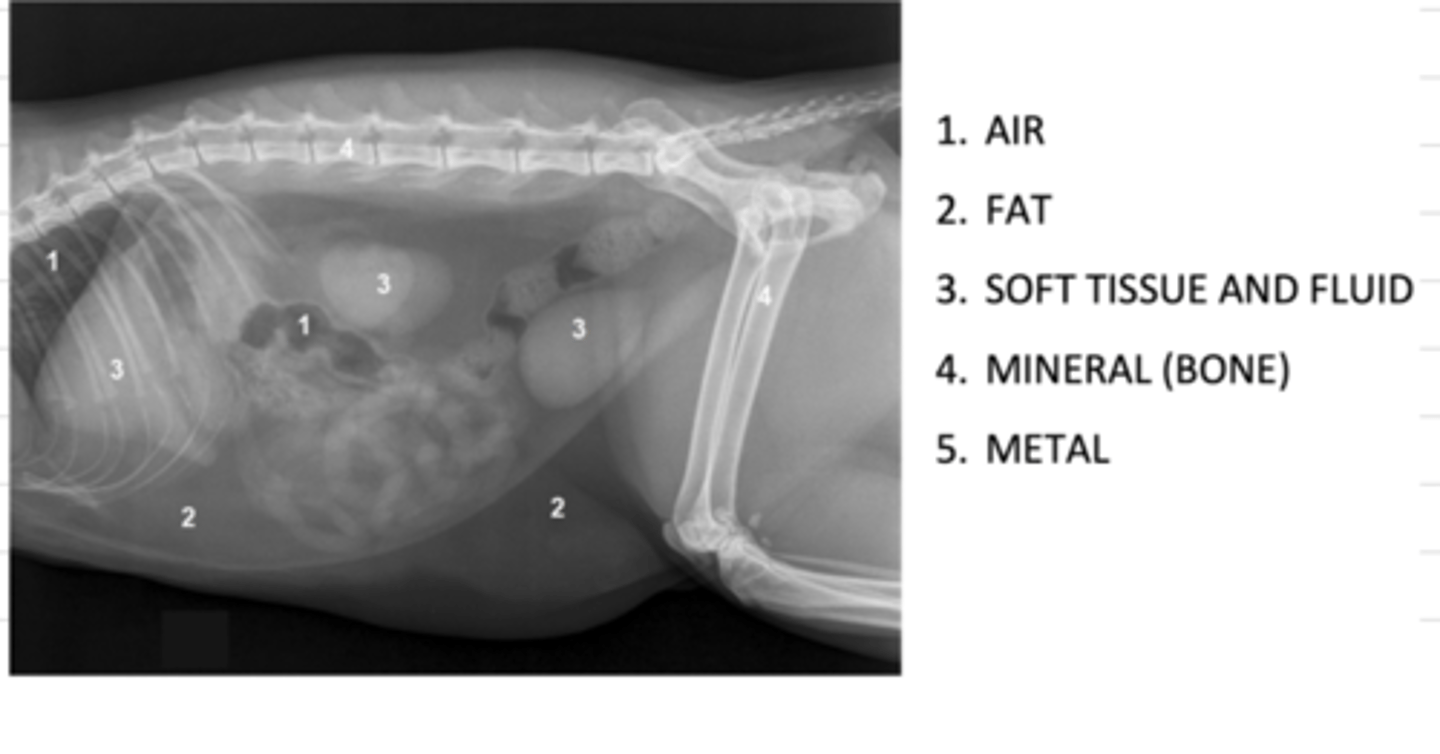

what are the 5 opacities of a radiograph, from most radioluscent to most radiopaque?

1. air

2. fat

3. soft tissue and fluid

4. mineral (bone)

5. metal

what are the 5 opacities of a radiograph?